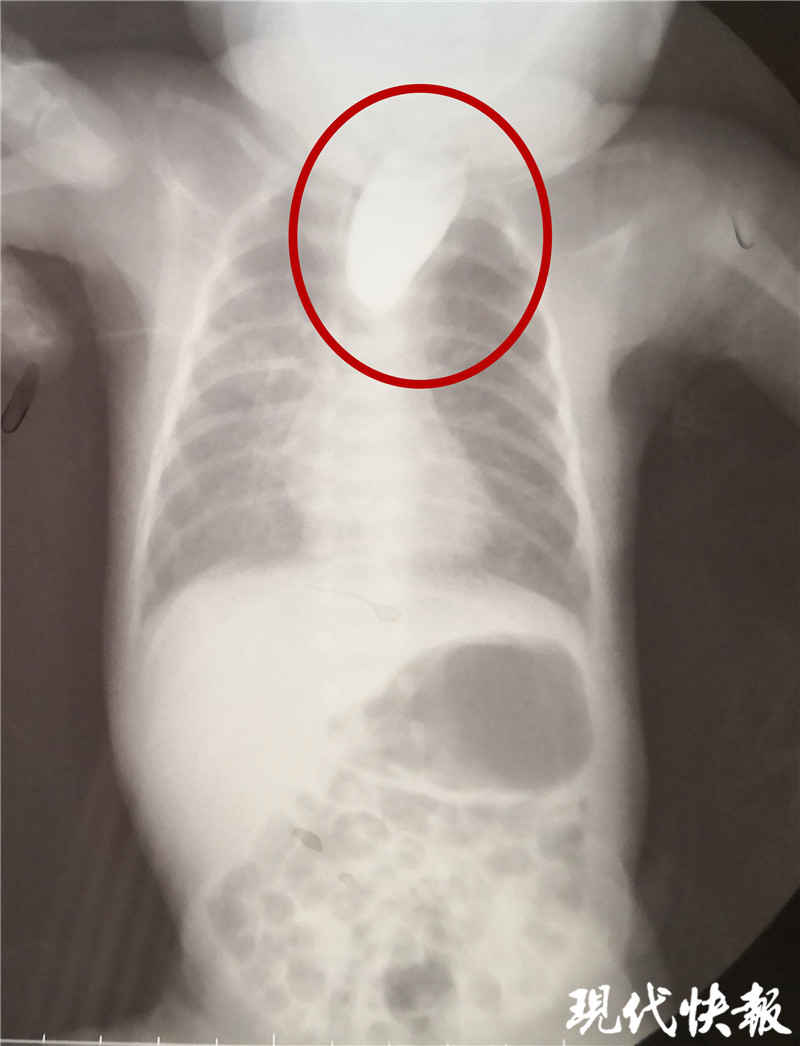

△食道閉鎖

現(xiàn)代快報(bào)記者了解到,9月8日,東東從當(dāng)?shù)蒯t(yī)院轉(zhuǎn)入淮安市婦幼保健院治療,檢查顯示東東的食道是個(gè)“死胡同”,明確診斷為食道閉鎖。“從片子上看,這個(gè)白色的造影劑到了食管上端就無(wú)法向下流了,說(shuō)明孩子的食管上端是不通的、閉塞的。同時(shí),孩子腸腔里面有氣體,這個(gè)氣體是通過(guò)氣道到食管的遠(yuǎn)端,到達(dá)胃和腸道內(nèi)。”淮安市婦幼保健院小兒外科副主任醫(yī)師夏順林說(shuō),這個(gè)寶寶如果不及時(shí)手術(shù),就會(huì)面臨兩個(gè)問(wèn)題,一個(gè)就是唾液咽不下去,會(huì)嗆入肺部形成吸入性肺炎,同時(shí)胃和食管遠(yuǎn)端與氣管相通,胃內(nèi)的胃酸容易反流到氣道里面,進(jìn)入肺部形成化學(xué)性肺炎。